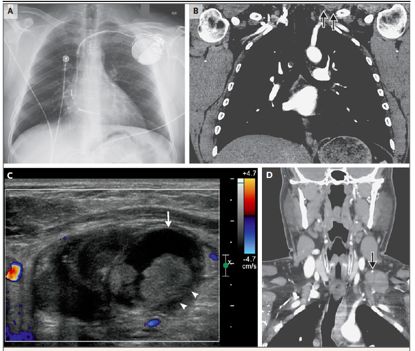

12 周前,患者在该院通过左头静脉放置了植入式心脏复律除颤器(ICD)(图 1)。植入后不久,他左手开始出现短暂的针刺样不适;患者之前也有过类似的症状,并伴有左臂尺神经分布区域的刺痛和感觉下降。神经电生理及 ICD 随访均提示正常。

转院后患者进行了一系列影像学检查。头颅 CT 平扫正常。胸部和腹部血管造影排除了肺栓塞和主动脉夹层,但显示左锁骨上区有部分可见肿块(图 2b)。颈部超声检查显示一混合回声肿块,直径 4.3 厘米,未见彩色血流信号(图 2c),以上描述支持血肿诊断。

对左侧颈部和锁骨上窝进行再次行超声检查,发现一个直径为 4.5cm 的混合性低回声病变,提示有是一个不断发展的血肿。

再次超声检查显示左锁骨上区有直径 3.9 cm 的混合性低回声肿块;左颈内静脉、锁骨下静脉、腋窝静脉、肱静脉和基底静脉未闭。颈部增强 CT 显示一个直径为 4.0 cm 的不均匀肿块,位于颈部左侧的软组织中,深至胸锁乳突肌,紧靠左侧颈总动脉和臂丛(图 2d)。肿块中可见小钙化。未见动脉或静脉阻塞的迹象。